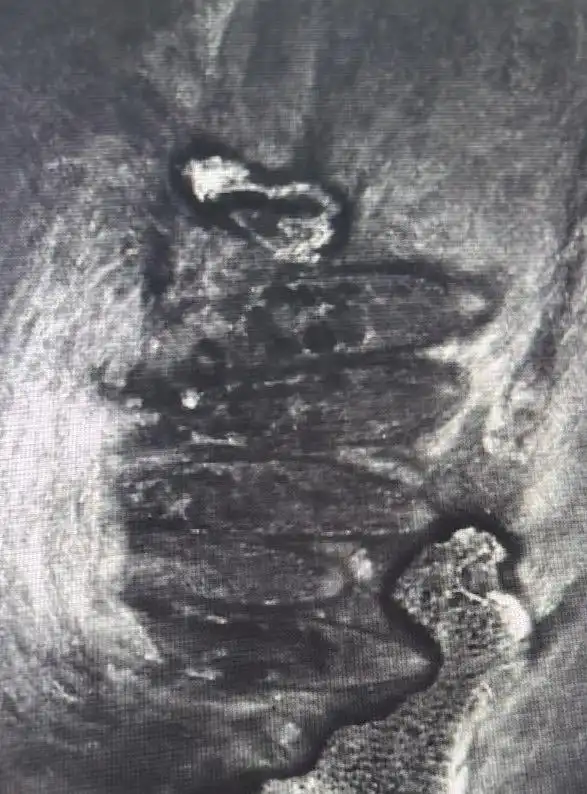

經(jīng)共聚焦顯微鏡檢測(cè),醫(yī)生在小浩雙眼18個(gè)毛囊中揪出86只蠕形螨,右眼39只、左眼47只的檢測(cè)結(jié)果讓醫(yī)護(hù)人員直呼罕見(jiàn)。“這簡(jiǎn)直就是螨蟲(chóng)在眼睛里安了家!”主刀醫(yī)生鄧軍表示,小浩長(zhǎng)期嗜好油炸食品、甜食,青春期油脂分泌旺盛,為螨蟲(chóng)提供了絕佳生存環(huán)境。